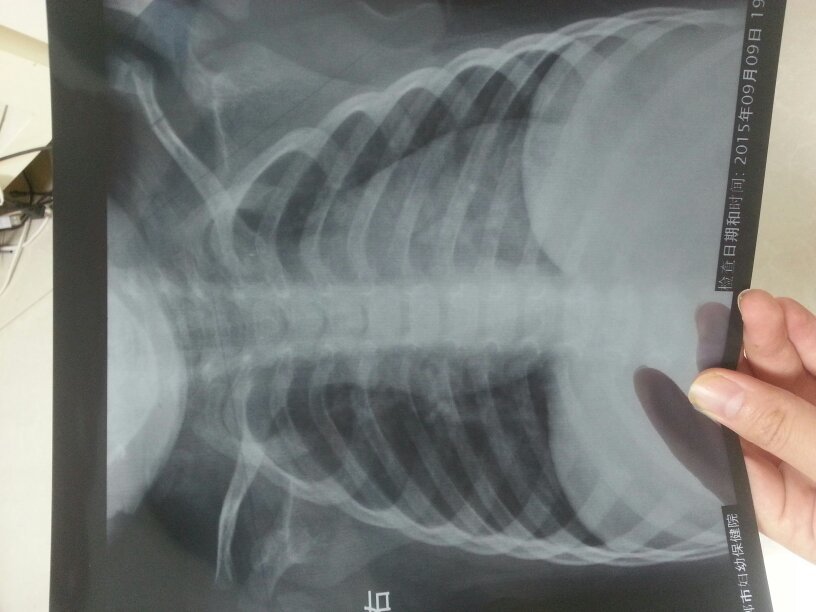

孩子今天昨天早上开始咳嗽 今天下午到医院拍了个胸片 大夫说肺炎需要输液 大家哪位是医生给看看有输液 孩子今天昨天早上开始咳嗽 今天下午到医院拍了个胸片 大夫说肺炎需要输液 大家哪位是医生给看看有输液的必要吗 吃药打针可以吗 点击展开 匿名用户 2015-09-09 21:08 推荐回答 肺炎必须厘医崭以尽快消炎为航殊主,而消炎最好的办过基法是输液,别为难孩子,应早作打算,以免延误。 扈乐心_e8qU 2015-09-09 21:21 宝宝知道提示您:回答为网友贡献,仅供参考。 为您推荐: 其他回答 输液好 匿名用户 2015-09-09 21:35 相关问题 10月大的宝宝做胸片有点肺炎,需要住院,输液不? 16个月婴儿,做胸片为双肺纹理增强,是不是肺炎?-咳嗽 我有个病人,刚满月,有黄疸,咳嗽,胸片提示支气管肺炎 处方是:1 先锋必2 茵栀黄3 维生素K1 不知道行